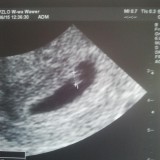

usg 12tydz

nie lubię lubię to | Osoby (34) które to lubią.Osoby które to lubią: paula_filip_szyszko, irka, robertt, teresa211186, mysia83, aniabrodawska, natalia198711091, ewa_rybaczuk, barbarus, tomek_dobosz, kornelia_zagawa, netika, rafal_bylinski, dorota_rzezniczak, joanna_pielach, emylka86, grazyna_sokolowska, beaM, maciejek_tryc, mmaarriioollaa, Aludka, joana_p, verona86, mikaa997, zdzislawa_sadowska, tata_pati, kamil_skwara, palka231, malwcia790, czarnecka_sandra, alfi, sebastian81, anastazja_paszko, kasztanka2.